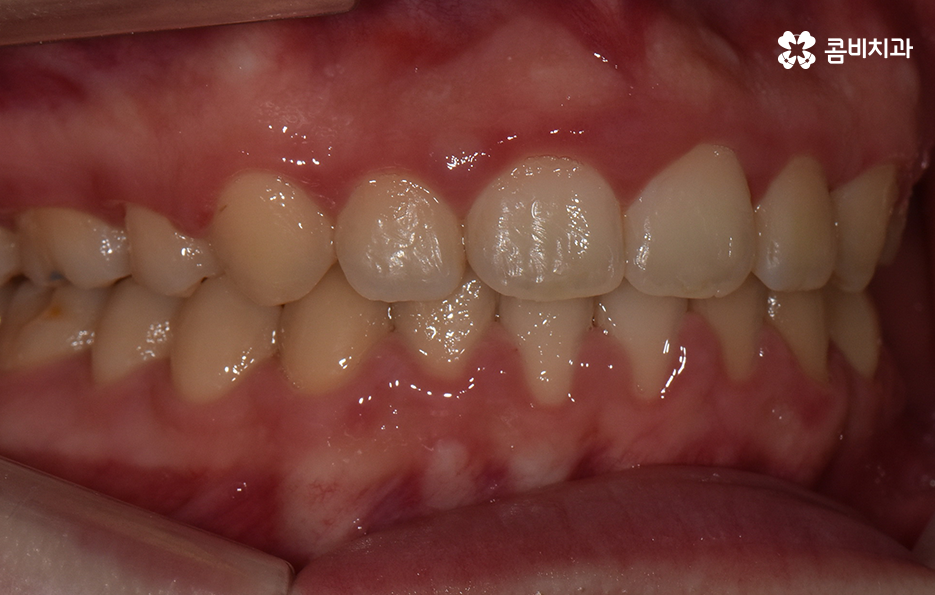

오늘 소개드릴 케이스의 경우 아랫니가 비교적 작기 때문에 교정을 통해 모아주고 윗니의 경우 측면으로 볼 때 더 잘 느껴지겠지만 다소 돌출된 상태이기 때문에 윗니는 발치를 통해 치아 이동 공간을 확보하여 돌출된 앞니를 안쪽으로 모아준 사례로 볼 수 있는데요

아랫니의 경우 치아 사이가 벌어져 있기 때문에 치아를 이동시킬 수 있는 공간이 이미 확보된 상태이고 윗니는 다소 돌출된 앞니를 안쪽으로 들어오게 하면서 심미선을 얼굴형에 조화롭게 맞출 수 있으며 그와 동시에 윗니와 아랫니의 교합도 고려한 치료 계획을 세운 것으로 간단하게 말씀드릴 수 있어요

사진으로 보더라도 아랫니 사이가 눈에 띄게 벌어져 있는 것을 확인할 수 있어요. 보통 웃을 때는 윗니 위주로 보이긴 하지만 아랫니가 이정도로 벌어져 있는 경우에는 콤플렉스로 여겨질 수 있어요